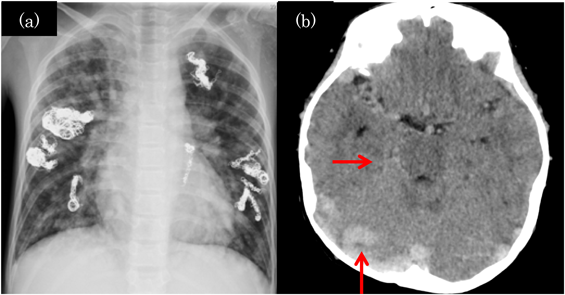

肺動静脈瘻を契機に発見され,脳脊髄動静脈瘻の破裂により死亡した遺伝性出血性末梢血管拡張症の小児2例Hereditary Hemorrhagic Telangiectasia Patients Detected by Pulmonary Arteriovenous Malformations: Two Pediatric Death Cases from Rupture of Cerebral and Spinal Arteriovenous Malformations